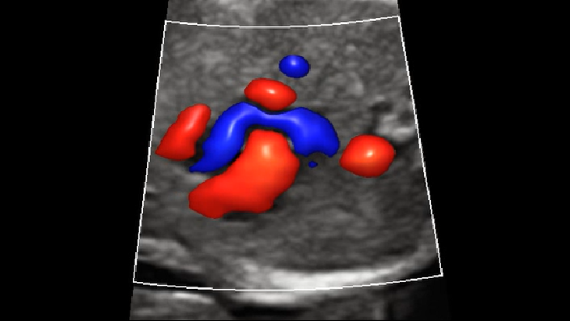

–°–Њ–≤–Љ–µ—Б—В–љ–Њ —Б —Б–Њ–≤—А–µ–Љ–µ–љ–љ—Л–Љ–Є —Г–ї—М—В—А–∞–Ј–≤—Г–Ї–Њ–≤—Л–Љ–Є —В–µ—Е–љ–Њ–ї–Њ–≥–Є—П–Љ–Є –љ–Њ–≤–Њ–µ —А–µ—И–µ–љ–Є–µ –Њ—В Mindray –њ—А–µ–Њ–±—А–∞–Ј—Г–µ—В –∞–Ї—В—Г–∞–ї—М–љ—Л–µ –Ј–∞–і–∞—З–Є –Ї–ї–Є–µ–љ—В–Њ–≤ –≤ –Ї–ї–Є–љ–Є—З–µ—Б–Ї–Є–µ –њ–Њ—В—А–µ–±–љ–Њ—Б—В–Є.

–°–Є—Б—В–µ–Љ–∞ DC-70 Exp —Б X-Insight –њ–Њ–Љ–Њ–≥–∞–µ—В —Г–њ—А–∞–≤–ї—П—В—М –њ–Њ–≤—Б–µ–і–љ–µ–≤–љ–Њ–є –Ї–ї–Є–љ–Є—З–µ—Б–Ї–Њ–є –њ—А–∞–Ї—В–Є–Ї–Њ–є —Б –ї–µ–≥–Ї–Њ—Б—В—М—О –Є —Г–≤–µ—А–µ–љ–љ–Њ—Б—В—М—О.

–Ю—Б–љ–Њ–≤—Л–≤–∞—П—Б—М –љ–∞ –≥–ї—Г–±–Њ–Ї–Њ–Љ –њ–Њ–љ–Є–Љ–∞–љ–Є–Є –њ–Њ—В—А–µ–±–љ–Њ—Б—В–µ–є –Ї–ї–Є–µ–љ—В–Њ–≤, –Ї–Њ–Љ–њ–∞–љ–Є—П Mindray —А–∞–Ј—А–∞–±–Њ—В–∞–ї–∞ —Б–Є—Б—В–µ–Љ—Г DC-70 Exp —Б X-Insight, —З—В–Њ–±—Л –Њ–±–µ—Б–њ–µ—З–Є—В—М eXpress Clarity, eXceptional Intelligence, eXceeding Experience.